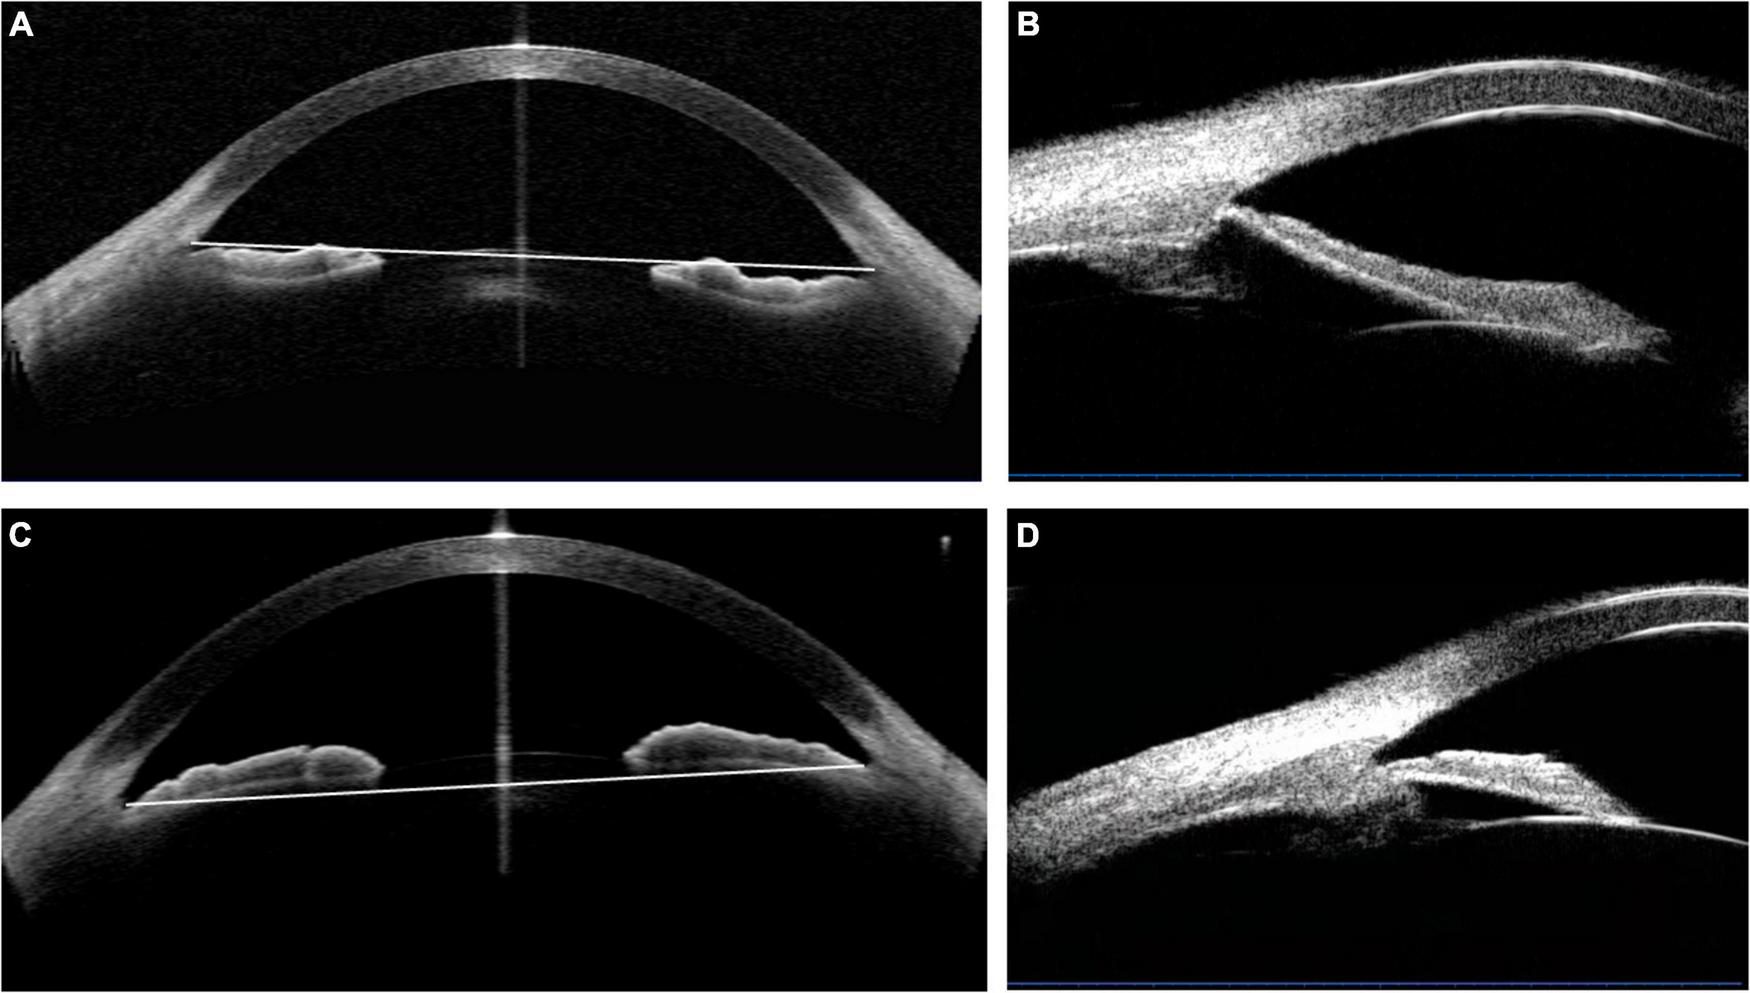

The selection process was shown in Figure 1. The concave iris was defined as a concave shape of the iris pigment epithelium, referring to a “bowing” away from the cornea; while the convex iris was characterized by a convex shape of the iris pigment epithelium, referring to that the mid-peripheral iris pigment epithelium is “bowed” toward the cornea (17) (Figure 2).

FIGURE 2

The determination of the concave and convex iris shape based on the anterior-segment optical coherence tomography (AS-OCT) or ultrasound biomicroscopy (UBM) images. (A,B) Concave shape iris: most part of iris locating behind angle-to-angle (ATA) with a concave shape of the iris pigment epithelium, referring to a “bowing” away from the cornea. And a wide sulcus could be detected in (B). (C,D) Convex shape iris: most part of iris locating before ATA with a convex shape of the iris pigment epithelium, referring to that the mid-peripheral iris pigment epithelium is “bowed” toward the cornea. Besides, convex shape iris with anteriorly positioned ciliary body was demonstrated in (D).